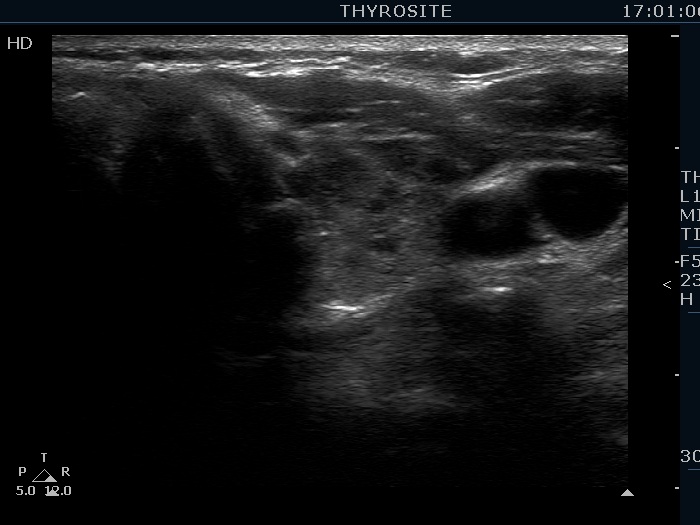

Second examination 19 months later (second row of images):

Comment. This is a typical presentation of a newly developed hypothyroidism regarding the change in echo pattern. Although the correlation between the echogenicity index and the hormonal status is week, in a particular patient, a developing hypothyroidism from an euthyroid state usually correlates with an increasing echogenicity index.Clinical data: This time the patient had no complaints, however the TSH was 16.8 mIU/L two month ago.

Palpation: no abnormality.

Laboratory tests: TSH 29.1 mIU/L, FT4 13.1 pM/L, aTPO 638 U/mL.

Ultrasonography. Compared with The previous examination, one change could be observed: the echogenicity index rose to 70-90%.

Daily 75 microgram levothyroxine was administered.